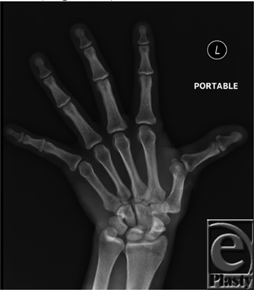

A 35-year-old man suffered a self-inflicted work injury from a circular saw on the dorsum of the thumb on his nondominant hand, sustaining a total transection of his extensor pollicus longus (EPL) and a concomitant dorsal capsule injury.

In addition to having an IP joint extensor deficit, our patient also presented with a significantly radially deviated thumb (Fig 1). This positioning of the thumb alerted us to a possible injury of the ulnar collateral ligament. However, our initial examination was limited due to significant pain, and we were unable to adequately assess this injury until we were in the operating room. To properly test for ulnar collateral instability, a valgus stress test is performed at 0° and 30° of flexion showing greater than 30° and 15° of movement, respectively. Often these injuries are associated with dorsal capsular tears.2 Once the patient was sedated, a proper examination was performed and no valgus laxity was noted and the collateral ligament was determined to be intact. As shown in the cover image, the patient clearly had a coexistent dorsal capsular tear with an exposed metacarpal head. Without repairing the capsule, the newly repaired EPL would sublux ulnarly and volarly, leading to a significant extensor lag.3 The recommendation is to repair the capsule separately from the EPL tendon that was performed using a 4-0 Ethibond in a horizontal mattress fashion.

| Figure 1. Radial deviation of the thumb is typical with a laceration of the extensor pollicis longus. |